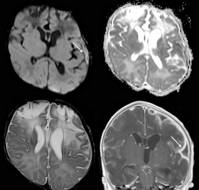

A report describes the case of a four-month-old male infant who presented with acute encephalopathy and symptoms of elevated intracranial pressure (vomiting, periods..

Acute disseminated encephalomyelitis (ADEM), also known as postinfectious encephalomyelitis is a rare immune-mediated pathology involving inflammatory demyelination ..

Herpes simplex virus encephalitis (HSE) is a treatable form of acute sporadic encephalitis with a high mortality rate of 50-70% if left untreated or inadequately tre..